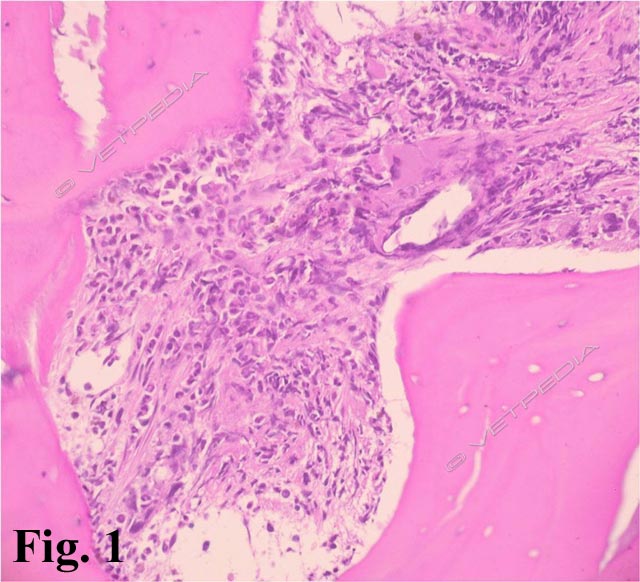

L’esame radiografico di norma si può eseguire senza sedazione; si può eventualmente eseguire una breve anestesia gassosa con induzione diretta. Viste le dimensioni della cavia, conviene eseguire di routine le proiezioni laterale e ventrodorsale di tutto il corpo, a meno che l’animale non sia gravemente debilitato e manovre stressanti poss...